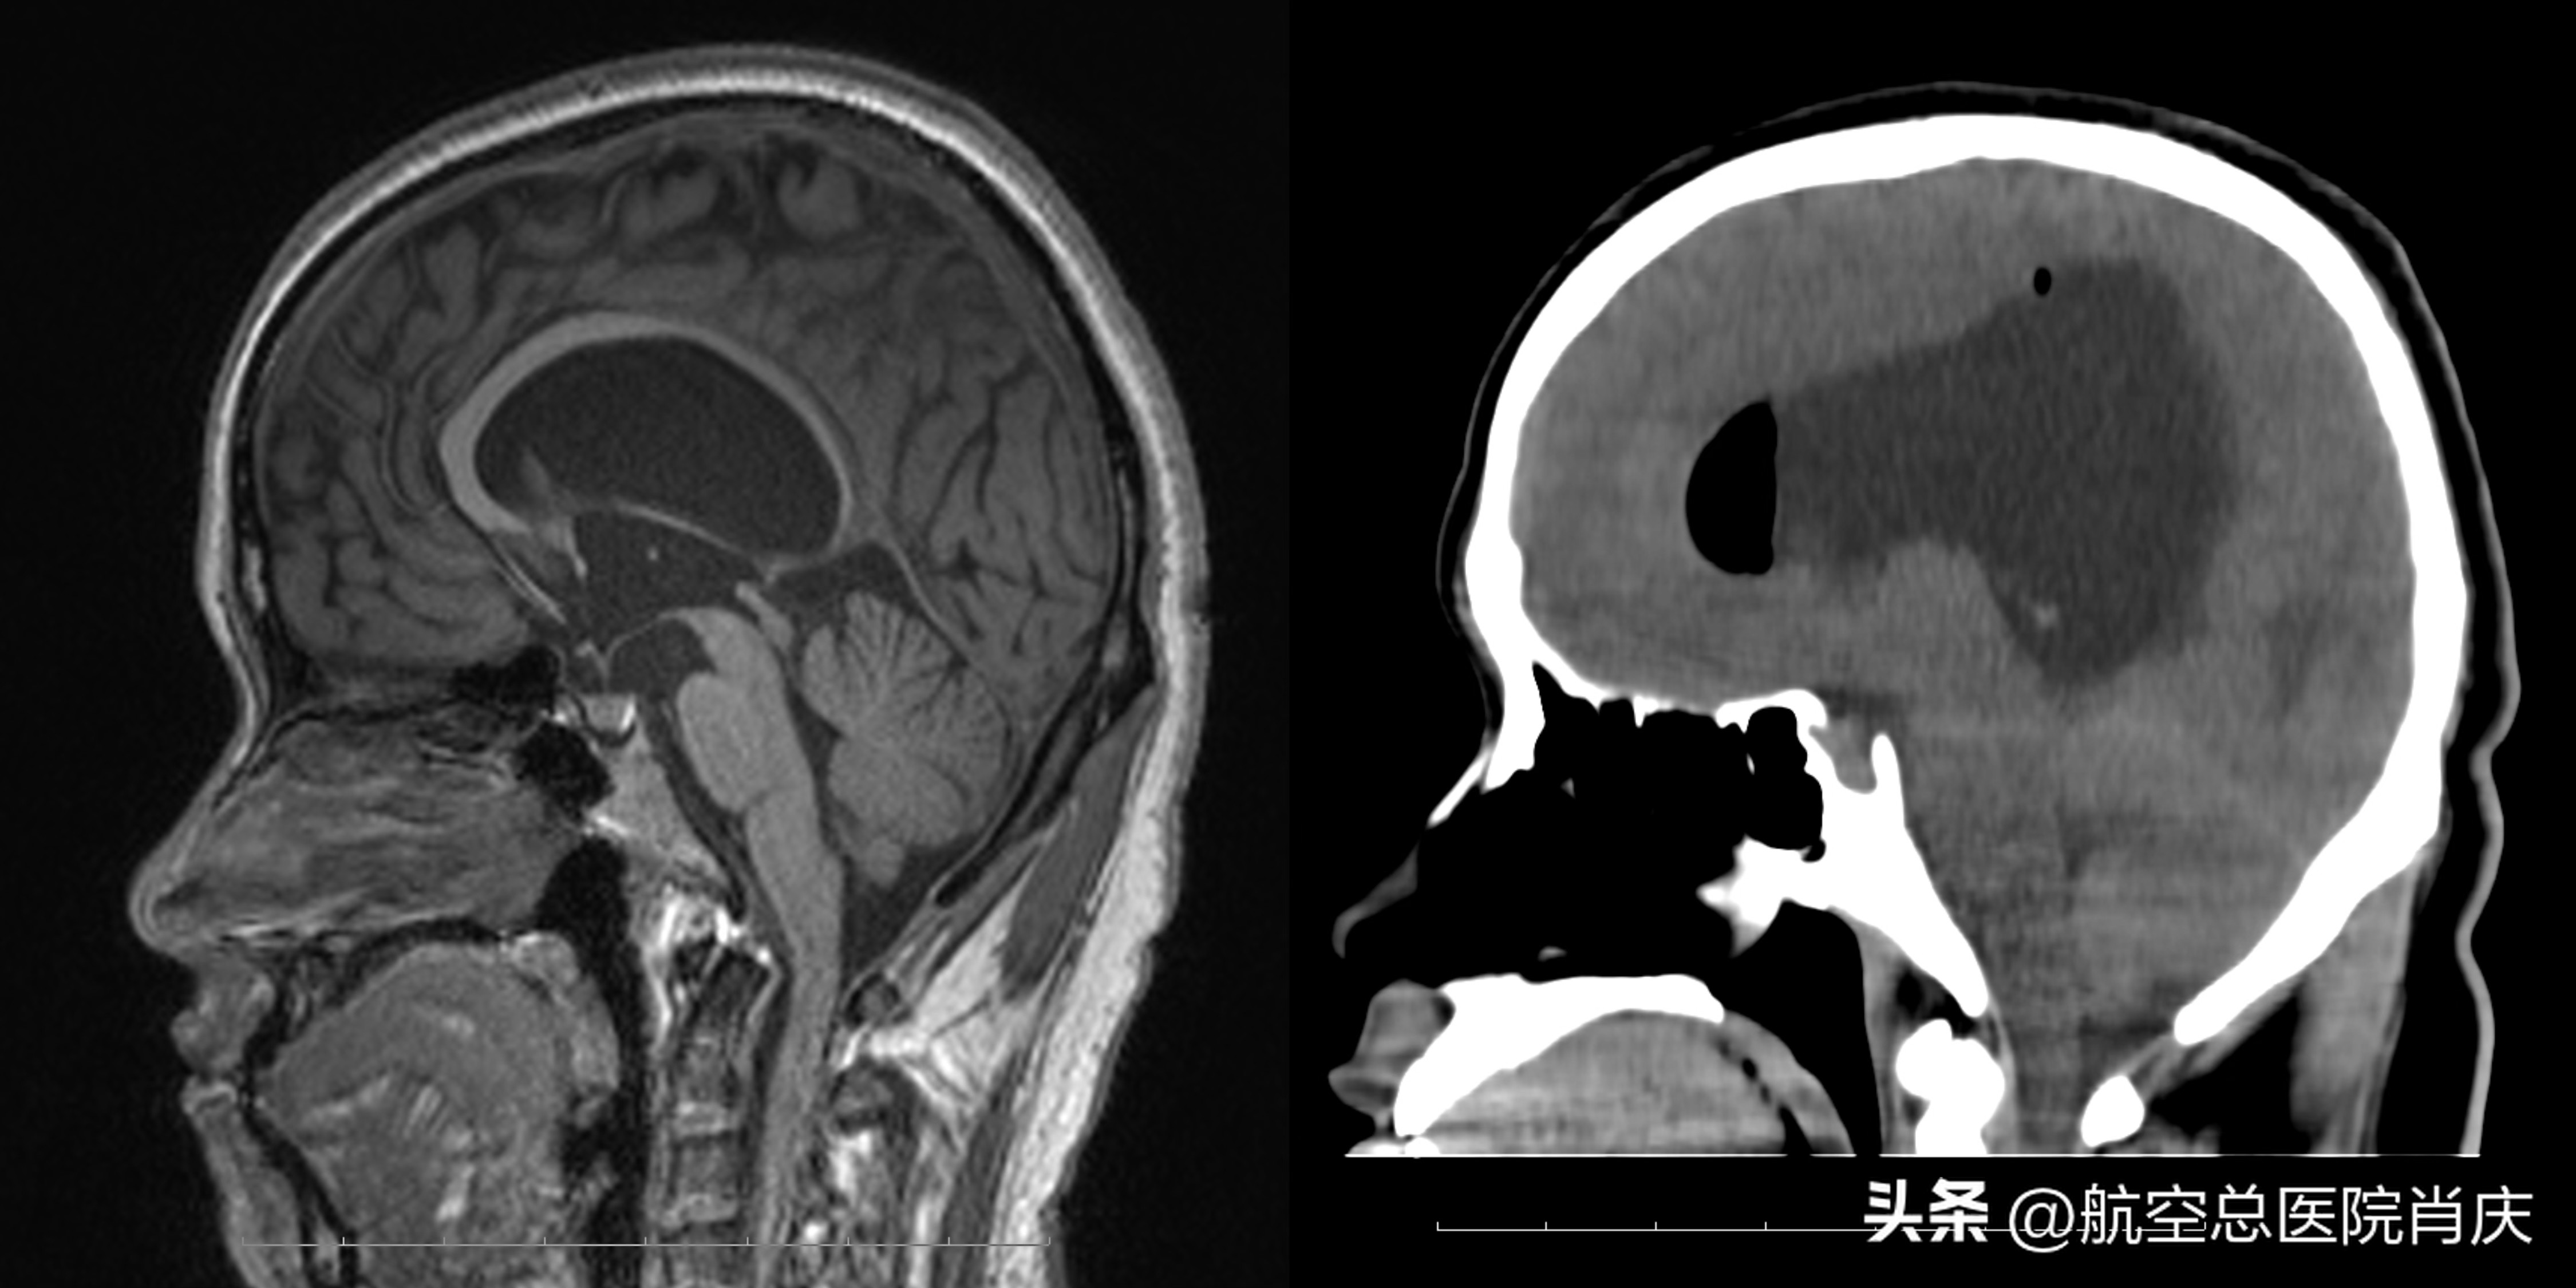

术前术后对比矢状位

确定了治疗方案,经过综合风险评估及科学严谨的术前准备,肖庆主任及团队为患者在全麻下行神经内镜检查术+神经内镜下第三脑室底造瘘术后+神经内镜脑室造瘘术。手术顺利成功,患者术后恢复良好,症状缓解,头颅CT检查明确术后脑室变小,历经16天的治疗,已经可以出院休养。